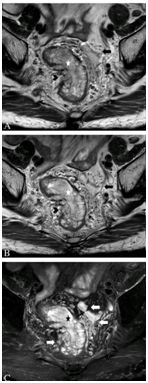

除腺癌外,直肠损害还包括良性肿瘤、肿瘤样表现和其它类型恶性疾病(表1)。上述情况的图像特征对诊断有帮助(图13)。

图13  A. 子宫内膜异位,轴位T2加权像显示左侧卵巢子宫腺肌瘤(星号),前侧直肠系膜筋膜(长箭头)为粘附于异位内膜的星状低密度信号影,伴直肠前壁增厚(箭头);B.直肠类癌,轴位T2加权像显示粘膜下层边界清楚肿物(箭头),伴孔状高密度信号影(长箭头);C.直肠间质肿瘤,轴位T1加权钆增强像显示粘膜下(箭头)肿物轮廓清楚且均匀强化(长箭头)。

直肠系膜淋巴结和髂内淋巴结属于N分期,密度信号和淋巴结形态较大小能更好的预测淋巴结受累,表现为不规则边界和不均匀密度信号(图14),94%受累淋巴结只有5mm大小。推荐高分辨薄层T2加权像鉴别波尔卡圆点淋巴结征象,表现为正常大小转移淋巴结内部低密度信号(图14B),通常阳性淋巴结位于原发肿瘤水平或之上,与头端引流有关。精确评估淋巴结状态很重要,阳性是新辅助放化疗适应症,CRM 1mm内淋巴结必需报告,可能会影响CRM。直肠系膜外或侧方盆腔淋巴结,如髂外淋巴结、闭孔淋巴结和后腹膜淋巴结,为M疾病,进展期下位直肠癌上述淋巴结阳性更多。

图14  直肠淋巴结转移。A.轴位T2加权像显示直肠前壁肿物(箭头)和直肠系膜淋巴结(长箭头),淋巴结边缘不规则,密度信号不均匀;B. 波尔卡圆点淋巴结征象,轴位T2加权像显示6-12点半环周肿瘤(长箭头),小的直肠系膜淋巴结呈点状低信号,与波尔卡圆点相似(箭头);插入图像显示波尔卡圆点淋巴结。